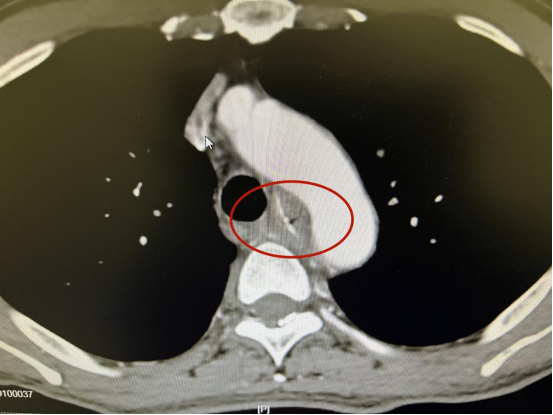

3月14日,中南大学湘雅三医院耳鼻咽喉头颈外科联合心胸外科、呼吸与危重症医学科、消化内科组成MDT团队,成功为一位66岁男性患者实施“鱼刺卡喉”清除手术。该患者经检查发现鱼刺穿透食管壁,直逼主动脉弓,并向腔外延伸,手术难度及风险极大。

据介绍,患者于3月13日在北京某医院检查出鱼刺卡喉后未予治疗,于14日慕名来到中南大学湘雅三医院耳鼻咽喉头颈外科门诊。当时,患者自诉7天前进食晚餐时误吞鱼刺一根,当即胸骨上窝出现持续性刺痛,自行采用“喝醋疗法”后疼痛症状未见明显改善且随之出现吞咽困难症状。经门诊胸主动脉CTA示:患者主动脉弓轻度粥样硬化,T4-6椎体水平有异物穿透食管壁,离主动脉弓仅2mm,情况十分危机。

手术径入后可见距门齿26cm处有一片状鱼刺嵌入食管壁内,与心脏同频搏动,凭借精准的控镜能力,通过反复调整异物钳角度及方向,最终以最小的前推力牢固钳夹住了鱼刺尾端,顺利将鱼刺取出并为患者进行了食道瘘清创及金属支架置放术。手术历时25分钟,术中失血仅约3ml,患者全麻清醒后诉胸痛感消失,术后患者持续禁食禁饮,护理团队通过胃肠管根据营养科制定的个性化营养方案为其进行肠内营养治疗,保证患者的能量供应。在医护团队的精心治疗下,患者恢复良好,无其他并发症发生。

众所周知,主动脉弓是连接升主动脉和降主动脉的一个大的动脉,是人体内最靠近心脏、内径最粗、压力最高的血管,它紧贴食道第二狭窄处,如果鱼刺在下行过程中穿破食道壁、扎进主动脉,易造成大出血,若救治不及时可能危及生命。